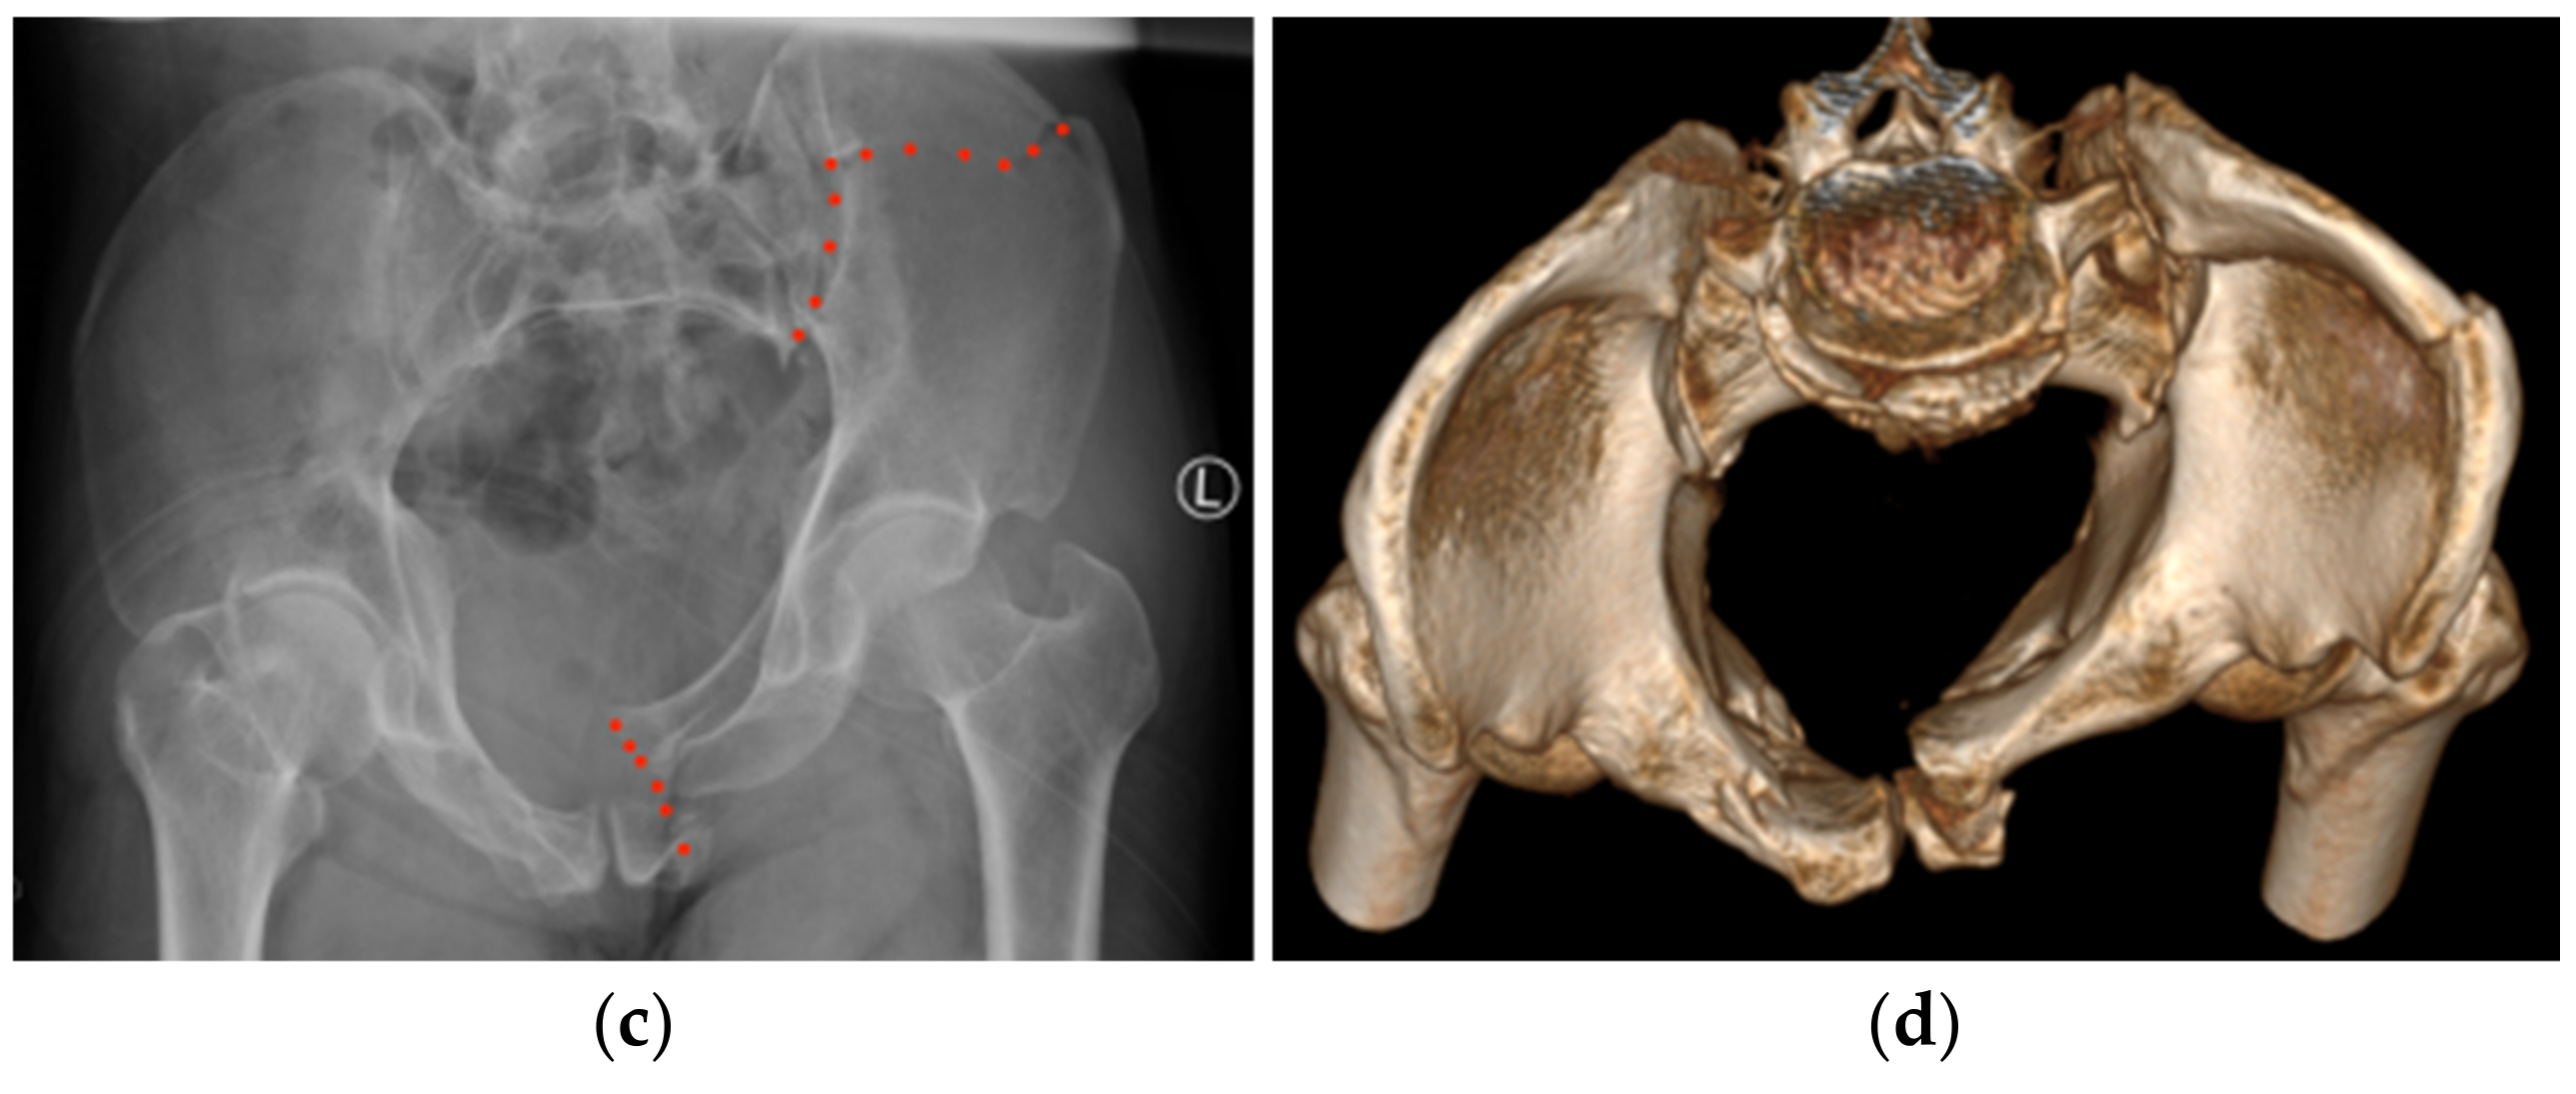

2. Case Report